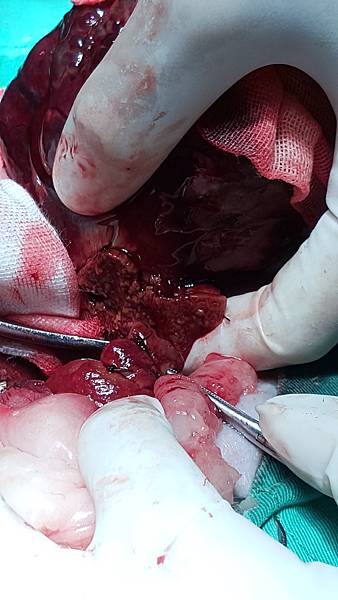

肝腫瘤切除 使用overlapping guillotine sutures+大倫牌止血棉

膽囊黏液囊腫摘除 使用血管夾結紮